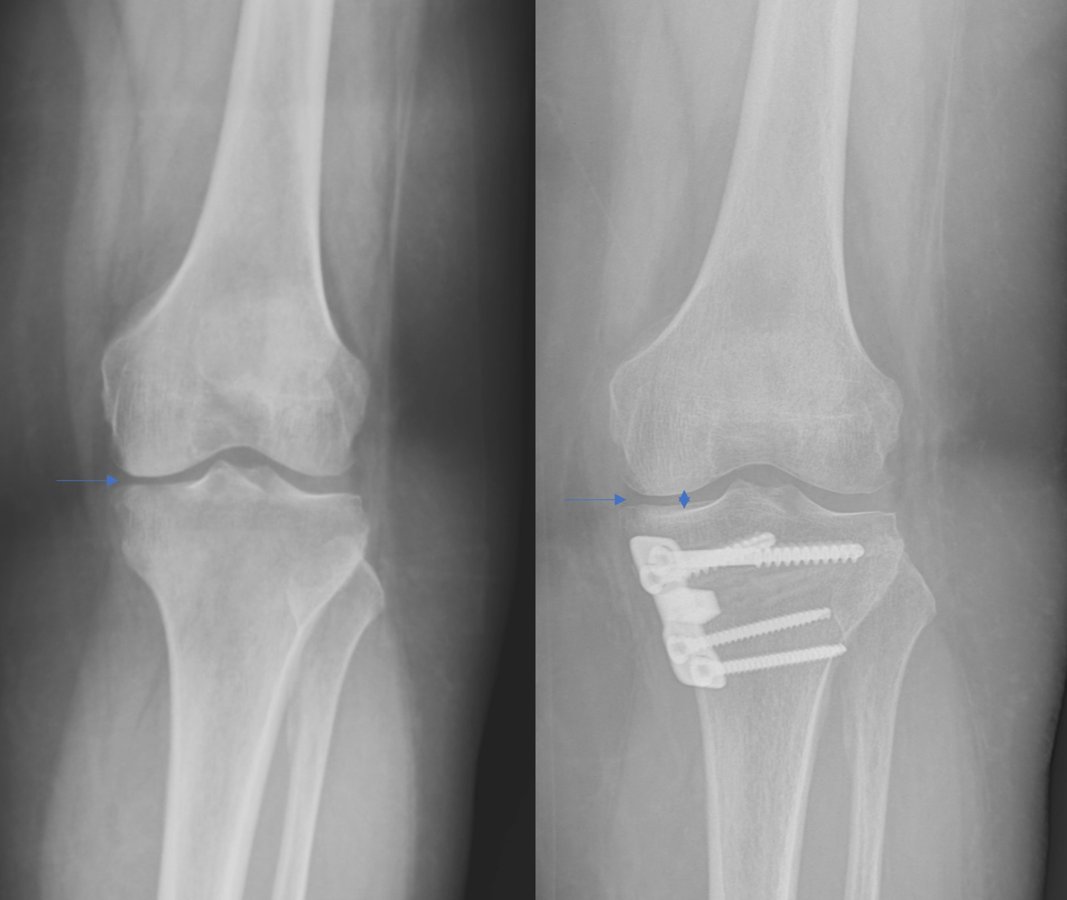

حول كاريا جراحة العظام وإعادة التأهيل عيادة كاريا جراحة العظام وإعادة التأهيل في موغلا ، تركيا تقدم رعاية العظام عالية الجودة ، بما في ذلك العلاجات الجراحية وغير الجراحية من قبل Assoc. البروفيسور الدكتور جيم يالين KILIN وفريقه. وهم متخصصون في الصدمات والإصابات الرياضية وجراحات تقويم المفاصل ، ولديهم خبرة في العلاج الطبيعي لإعادة التأهيل.